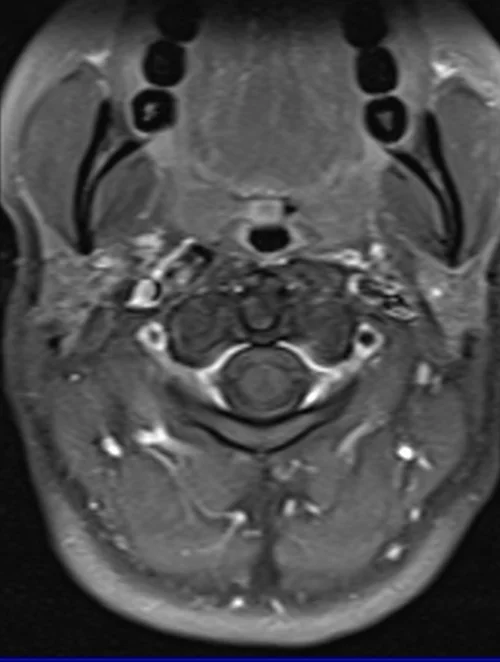

MRI cervical spine T1 FS axial images